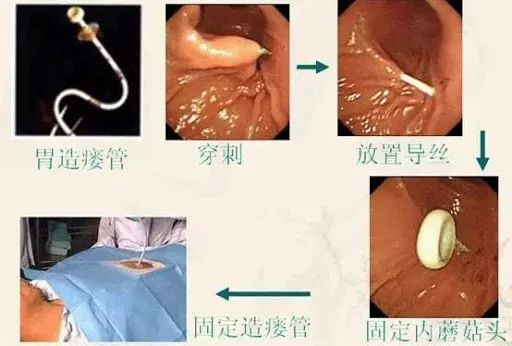

受此启发,如今医学上也有专门的胃造瘘术来治疗疾病。只不过它是解决食管癌晚期食管管壁脆弱病人的吃饭问题而设置的。它是将胃造瘘管刺穿腹部的皮肤,在内窥镜的探索下在胃部放置造瘘管,从外部给予人体必需的营养物质,提高人的生活质量,给予胃部所需要的充足营养,减少患者的不适。

人体进行胃造瘘手术的过程

类似地,在胃造瘘的手术前,需要对患者进行适当麻醉处理,尽可能减少患者的痛苦。而那些因为进食困难的患者,也经过胃造瘘手术打开了生命通道。